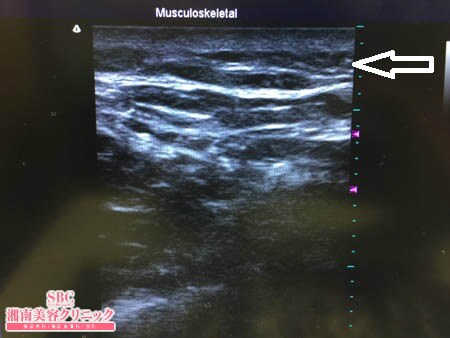

いつものように3Dタッチビュー(超音波)で

皮下脂肪層を評価してみましょう。

今回はタッチビューを用いて

手術終了直前に皮下脂肪の状態を

目で見て確認していますので

皮下脂肪の取り残しがない状態での

手術の終了となりましたので